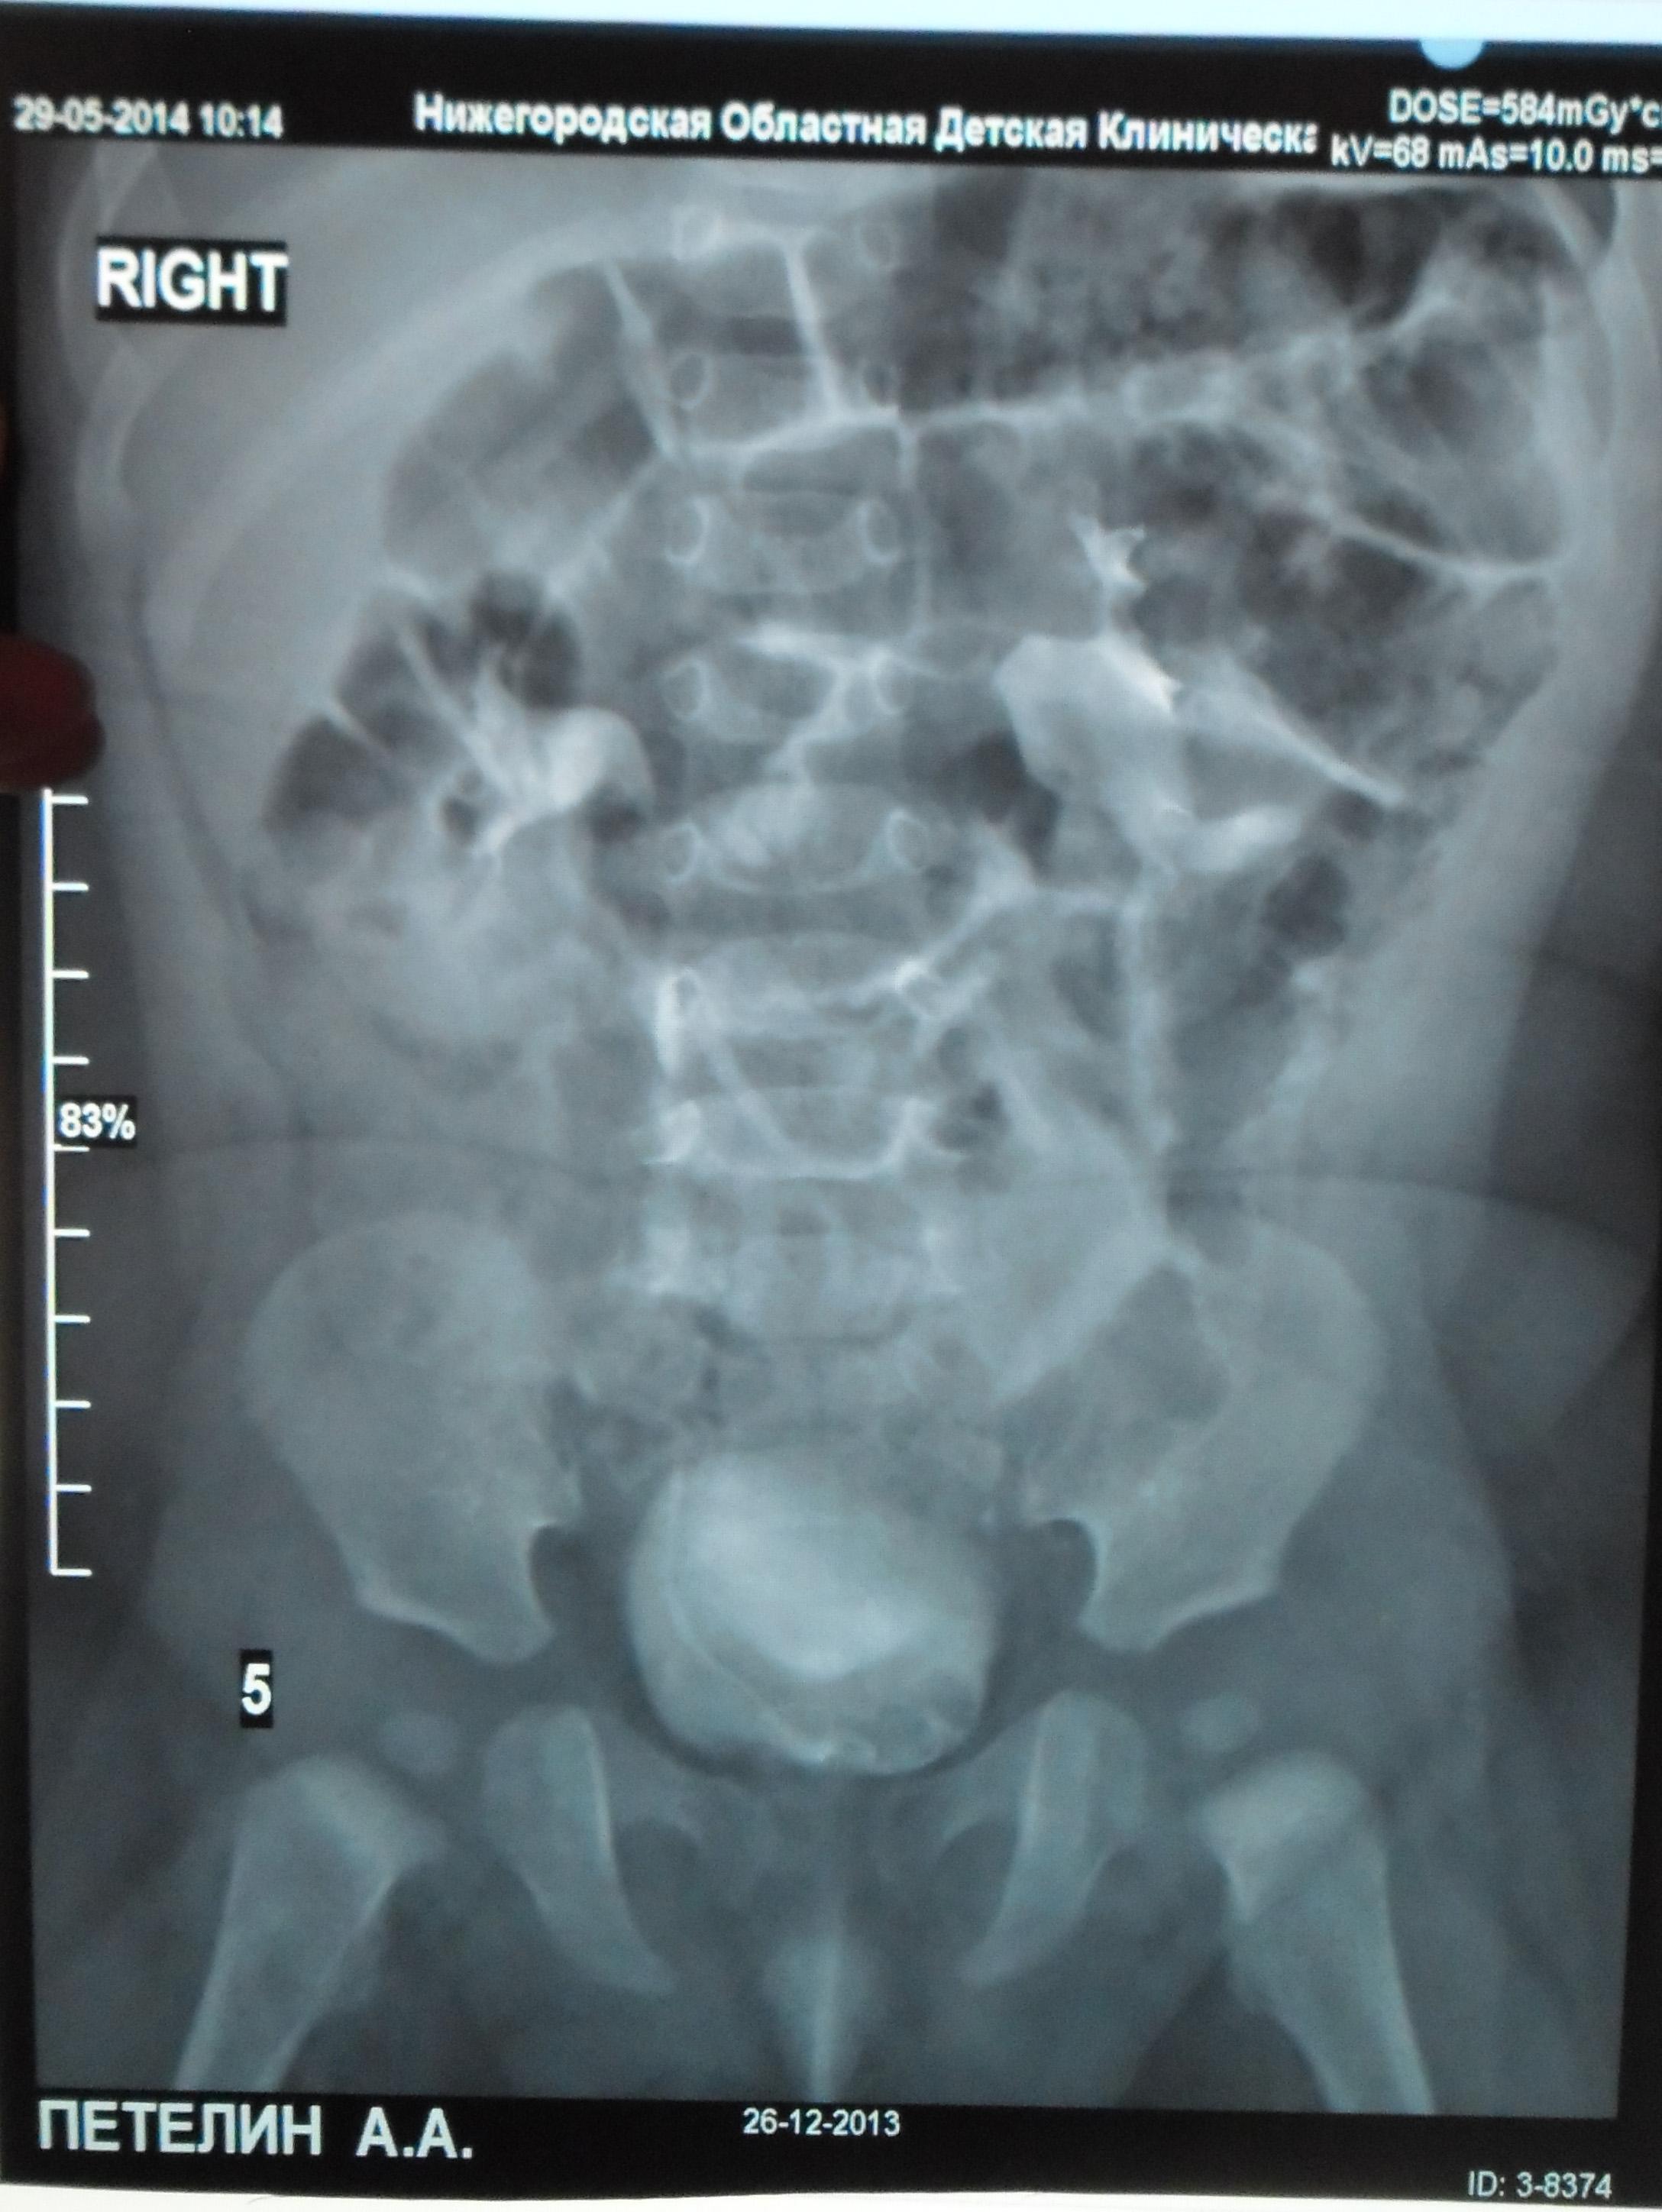

Моему ребенку 1 год 1 месяц. Во время беременности у плода было обнаружено увеличение лоханки слева - 9мм. Далее по результатам УЗИ после рождения максимальное увеличение достигало 17 мм. В 5 месяцев проходили урологическое обследование, результаты цистографии: мочевой пузырь округлой формы. Контуры ровные. ПМР нет. ЭЭД-1,2МЗВ; урографии: рентгеноконтрастных теней конкремента нет, почки в типичном месте, размеры сохранены, структура ЧЛК справа не изменена, слева пиелоэктазия, подвижность допустима, функция сохранена, ЭЭД – 0,4 МЗВ. По последнему УЗИ (1 год) увеличение лоханки слева - 28 мм. Мочеточники и сама почка в норме. Результаты анализов мочи за этот год хорошие (сдавали ежемесячно). В чем могут быть причины данного явления и чем это грозит малышу?

Ответ врача

В данном случае - сужение лоханочно-мочеточникового сегмента и\или добавочный сосуд(слева). Но выделительная функция почки сохранена. В данный момент целесообразно наблюдение, но в дальнейшем - не исключено хирургическое вмешательство.